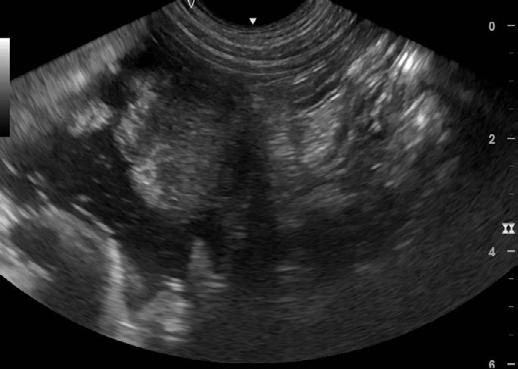

Pearl had a check up on 12.9.2024 and approximately 5 months after starting treatment her weight is now 24.2 kg. Pearl is extremely bright, alert, active and is eating very well. We sedated her to perform ultrasound to assess her progress.

The Ultrasound ( Figures 4) shows there are still some areas with thickening but they are much smaller than previously. I have recommended she stay on medication for another 3 months and then we will repeat the ultrasound.

We have continued Pearl on posaconazole 5mg/kg SID, Azithromycin 10mg/kg SID and Metalaxyl-M (Solitaire 240 ME fungicide 240 g/l) 6mg/kg BID.